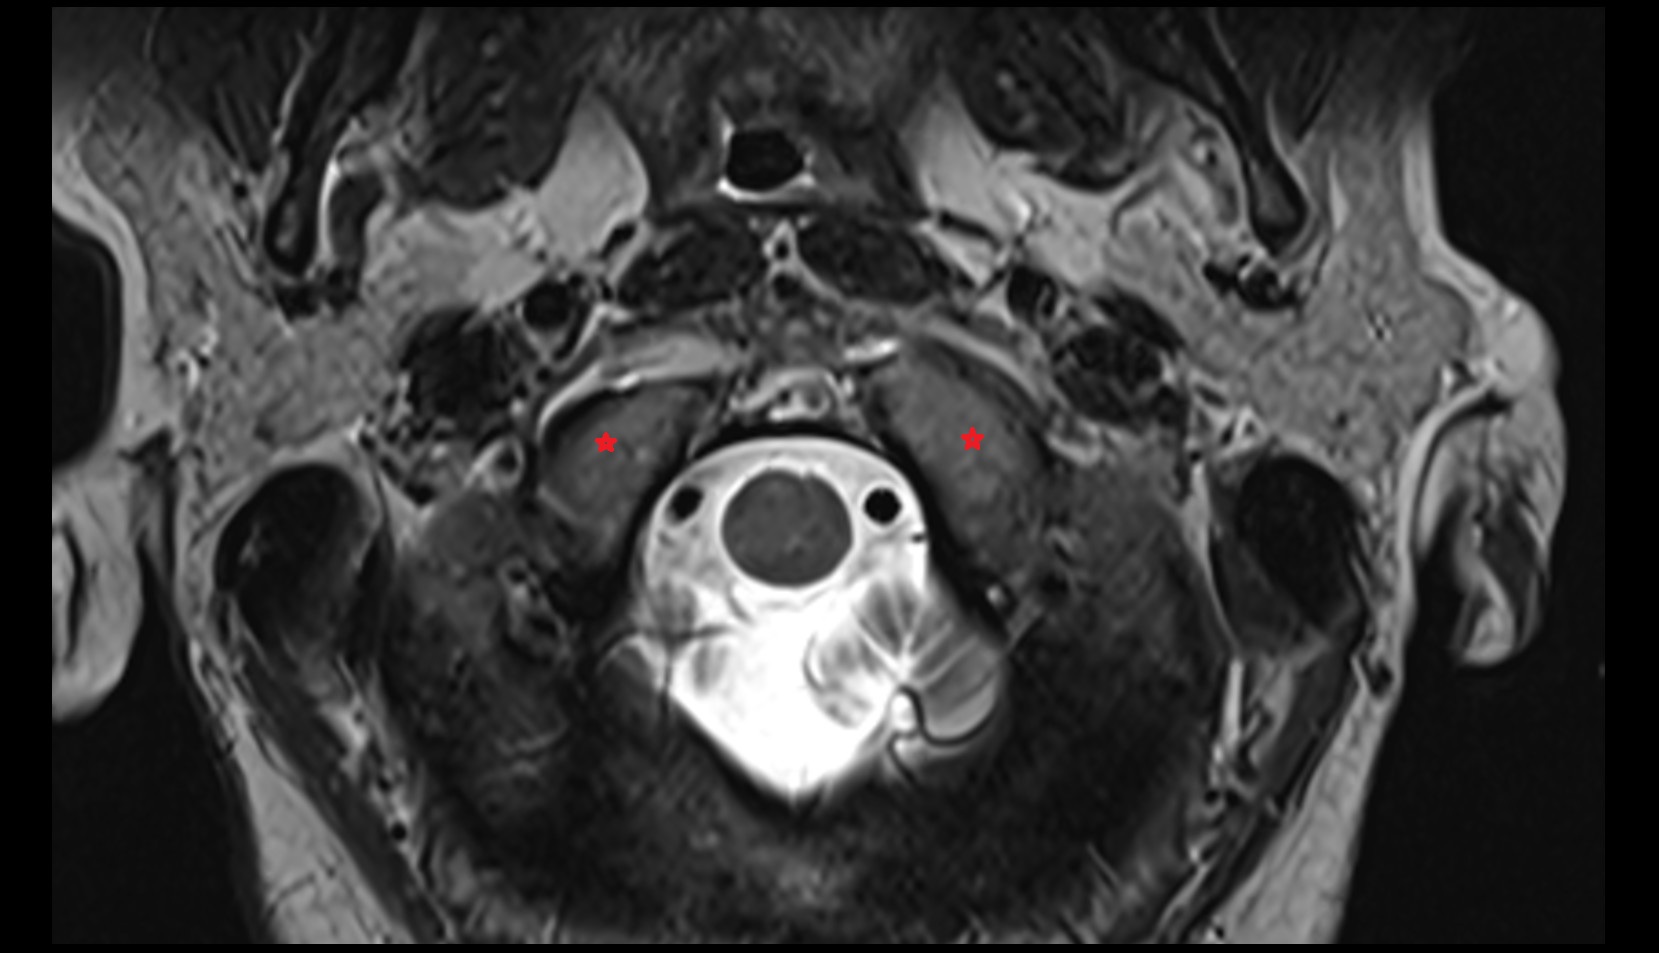

- Peripheral zone of prostate

- Anterior Fibromuscular Stroma of prostate

- Central zone of prostate

- Transitional zone of prostate